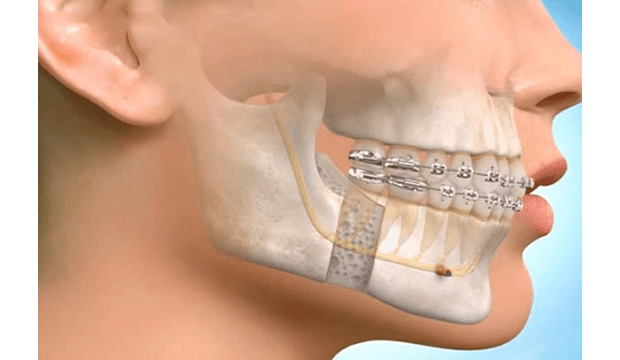

Çoğu durumda, ortodonti uzmanı ameliyattan önce dişlerinize diş teli yerleştirir. Diş telleri genellikle ameliyattan 9 ila 18 ay süre ile dişlerinizi ameliyata hazırlarken, dişlerinizi seviyelendirmeyi ve hizalamayı sağlar.

Ortodontist ve çene cerrahı, tedavi planını geliştirmek için birlikte çalışır. Dişlerin ve çenelerin röntgenleri, resimleri ve modelleri, bu ameliyatın planlamasının bir parçasıdır. Bazen oklüzyonün (alt- üst dişler arasındaki kapanış) tam sağlanamadığı durumlarda ,ilgili dişlerde selektif mölleme ( aşındırma ) yada kaplama tedavisi uygulana bilinir.

Çene cerrahı, çene kemiklerinde kesiler (osteotomi) yaparak çeneleri doğru pozisyona getirir. Çene hareketiniz tamamlandıktan sonra, kemikleri yeni (planlanan) konumlarına sabitlemek için kemik plakaları, vidalar, teller ve lastik bantlar kullanılır. Diş teli için kullanılan bir braketten daha küçük olan bu vidalar zamanla kemik yapısına entegre (kaynaşma) olurlar.